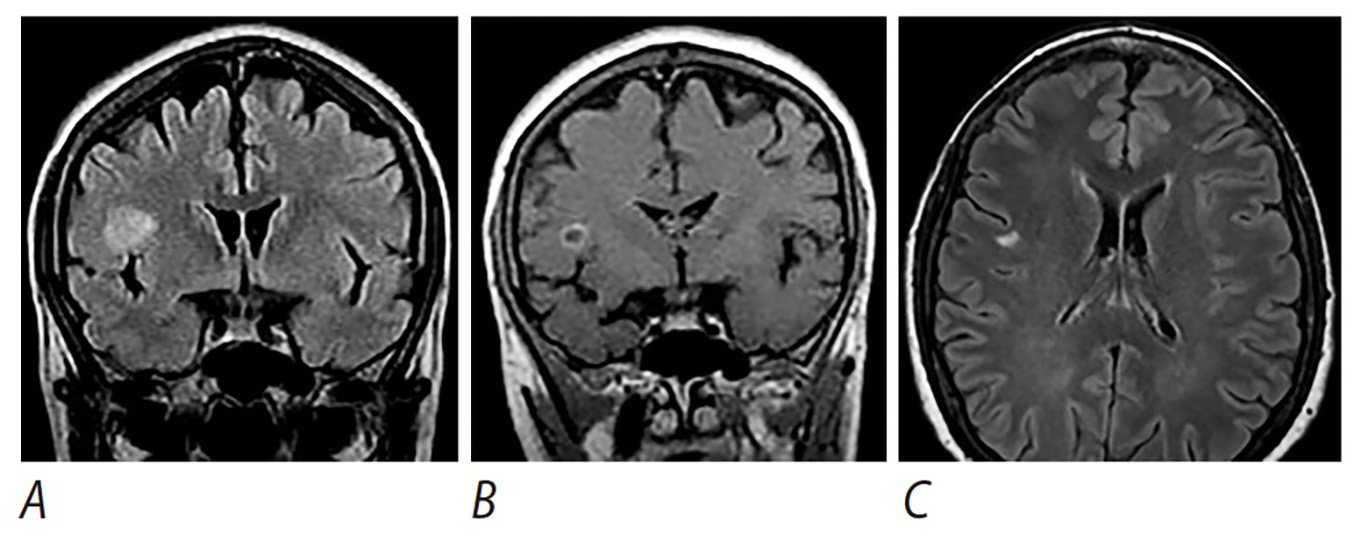

Рис. 1. Изменения в головном мозге пациентки З.

А, В — первичное обследование: А — Т2-FLAIR-взвешенные изображения в корональной плоскости; в правой лобной доле визуализируется очаг с высокой интенсивностью сигнала; В — Т1-взвешенные изображения в корональной плоскости после внутривенного введения гадолиний-содержащего контрастного препарата; отмечается кольцевидное накопление контрастного препарата очагом. С — изменения очага через 3 года: Т2-FLAIR-взвешенные изображения в аксиальной плоскости; отмечается уменьшение в размерах очага в правой лобной доли.

Fig. 1. Brain changes in patient Z (female).

A, B: initial study. A: T2-FLAIR-weighted coronal images; in the right frontal lobe, a high-intensity lesion is visualized. B: T1-weighted coronal images after intravenous use of a gadolinium-containing contrast agent; the lesion demonstrates ring enhancement. C: lesion changes at 3 years; T2-FLAIR-weighted axial images: the right frontal lobe lesion has decreased in size.

Таким образом, при первичном обследовании в 2011 г. у пациентки был выявлен единичный крупный очаг в правой лобной доле, окружённый тонкой полоской отёка и накапливающий контрастный препарат в виде кольца, что указывает на нарушение гематоэнцефалического барьера. При последующем наблюдении отмечается уменьшение этого очага.